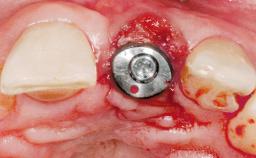

Immediate Flapless Placement of an Implant in a Maxillary Left Central Incisor Site

A 42-year-old female patient was referred to our clinic at the School of Dentistry of the University of São Paulo in November 2004, presenting a deficient restoration in the upper left central incisor. The clinical examination revealed no gingival retraction or any signs of gingival inflammation and, therefore, previous periodontal treatment was not considered. The patient presented a high lip line at full smile and a thin tissue biotype. This combination characterized a high-risk situation from an anatomic point of view, which required careful preoperative planning and cautious surgical execution.

Placement Protocol Immediate implant placement

Tooth Site Maxillary incisor or canine

Loading Protocol Immediate

Retention Screw-retained Screw-retained